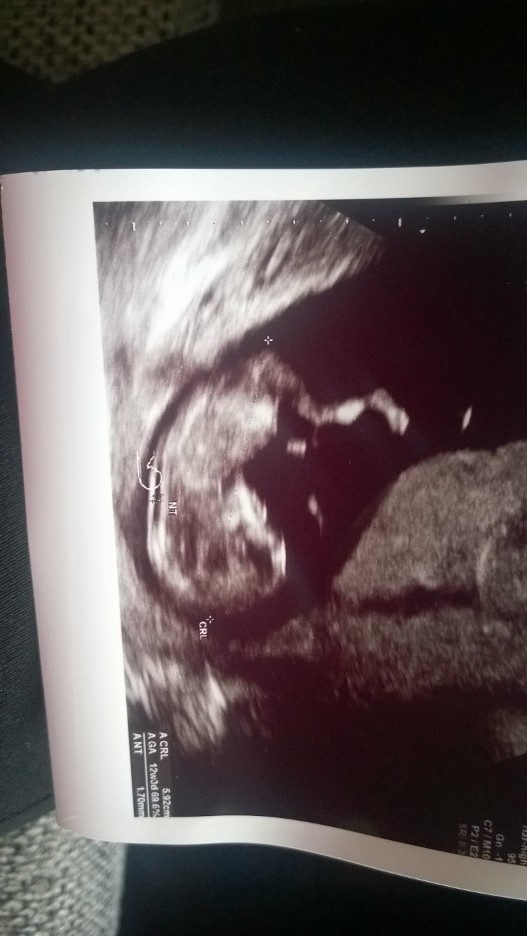

Ufff już po USG :)

Wszystko z dzieciaczkami dobrze. Jedna dzidzia ma 5,6 cm a druga 5,92 cm, przezierność też w porządku...bardzo ruchliwe ;) Kocham nad życie :)

• 12 tydz..JPG

12 tydz..JPG

127,7 KB · Wyświetleń: 123